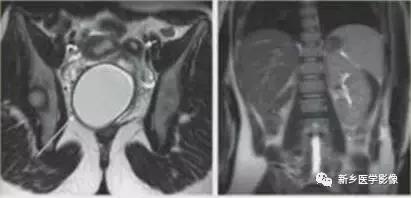

上图:双子宫:双侧子宫及宫颈完全分离

双子宫:双侧子宫完全分离,右侧阴道积血(阴道斜隔),宫腔积血,呈长T2信号。

右侧先天性肾缺如。